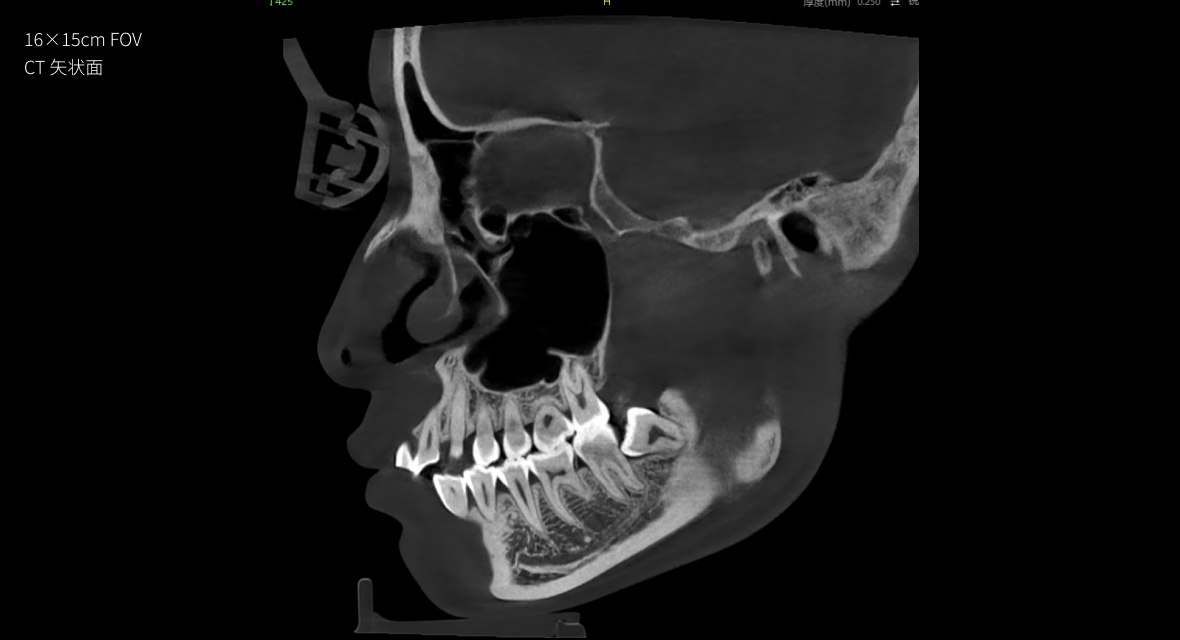

• CT

CT

16×15cm

非拼接大视野

28lp/cm

高精准

Physics-driven系列伪影校正算法

实现高清精准成像